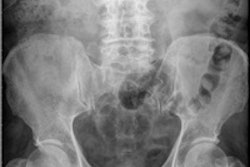

The participants were asked about their confidence in interpreting a scan for common findings. For a chest x-ray, only 14.4% said they were confident about their interpretational skills, whereas the equivalent figures were 27.9% for an abdominal x-ray, 62.5% for an x-ray of a shoulder, 52.9% for an x-ray of a leg, and 66.4% for an x-ray of an ankle.